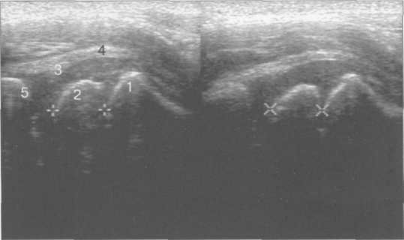

Рис. 19.83. Область хрящевого большого вертела (11 мес).

1 — контур шейки бедра; 2 — хрящевая зона области большого вертела; 3 — контур диафиза бедра.

Рис. 19.84. Боковой доступ, сканирование продольно вдоль шейки бедра (7 лет).

1 — шейка бедренной кости; 2 — ядро апофиза большого вертела; 3 — край головки бедренной кости.

Рис. 19.85. Боковой доступ, продольное сканирование тазобедренного сустава (2 года).

1 — шейка бедренной кости; 2 — ядро оссификации головки бедренной кости; 3 — хрящевой лимбус; 4 — хрящевая часть головки бедренной кости; 5 — контур крыши вертлужной впадины.

При латеральном доступе осуществляют преимущественно продольное сканирование. Наиболее выступающий костный фрагмент — большой вертел (рис. 19.83—19.85). Сразу над ним кнаружи определяются вертельные сумки, которые обычно в норме не дифференцируются, а также латеральная часть lig. iliofemorale и суставная капсула. Размеры подкожной вертельной сумки около 4—6×2—4 см.